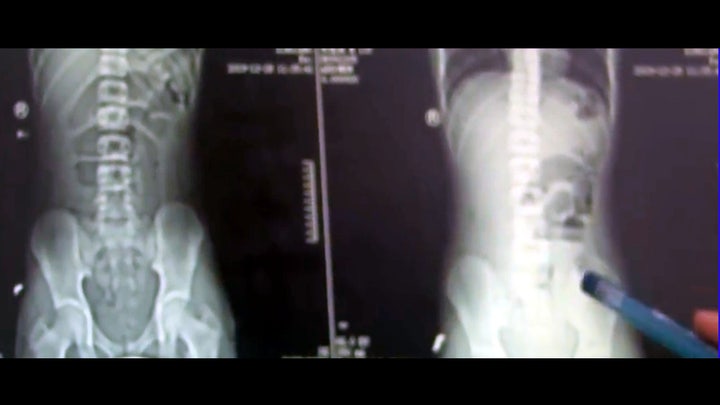

“Around 3 a.m. while I was on call, a 13-year-old boy was brought in with sudden abdominal pain,” Dr. Zhang Haiyang, the teen’s doctor at First Affiliated Hospital of Xinxiang Medical University, told the news outlet. “X-rays pointed to bowel obstruction. While inspecting his intestines, we discovered two solid objects, one larger and one smaller. These two objects were causing his obstruction.”

Doctors found two objects obstructing the teen's bowels, which they learned were tapioca balls. (AsiaWire)